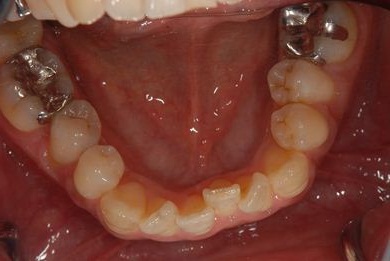

インプラントの症例写真 IMPLANT

インプラント治療+セラミック治療

| 治療内容 | インプラント1本、メタルボンドセラミッククラウン1本、オールセラミッククラウン2本(オールセラミック用土台2本) | ||||||||||||||||||||||||||||||||